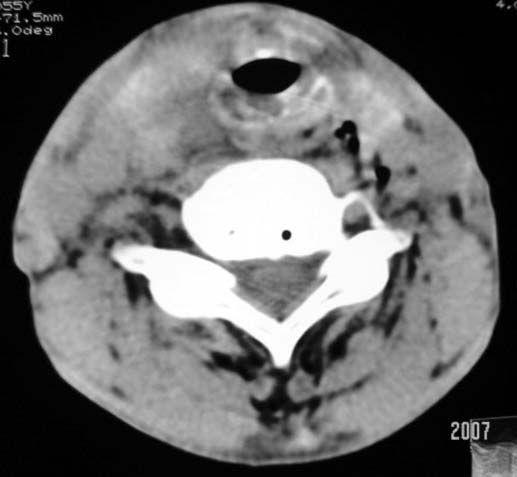

以下是引用dyqct在2007-4-20 16:19:00的发言:[br]考虑:1、左侧梨状窝区破裂伴左颈深、浅部气肿。[br] 2、右侧甲状腺区血肿(请追问病史是否伤及右颈部)。[br] 3、建议病情稳定后增强扫描除外右侧甲状腺腺瘤。